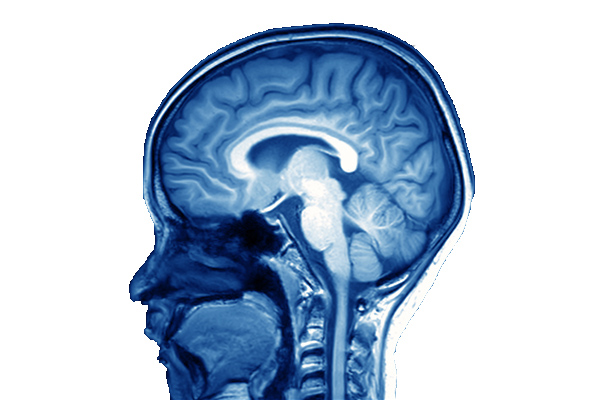

Bacterial meningitis is a life-threatening infection of the linings or meninges of the brain and spinal cord. Survivors may experience...